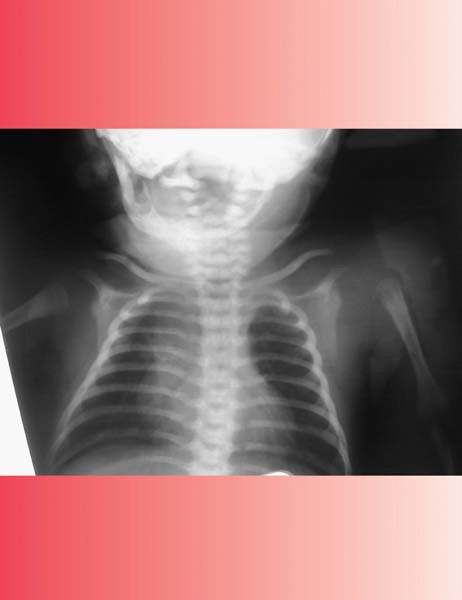

|  |

| ▪ FIGURE 10-2 Note lateral translation of the proximal humerus on this routine chest radiograph of a child with multiple medical problems in the NICU. The diagnosis of a septic shoulder was confirmed by ultrasound. |

examination by a limb that appears painful when moved. In the absence

of an obvious fracture on radiographs an ultrasound should be

performed, which may demonstrate a septic shoulder or subperiosteal

collection. Significant intraarticular pus may cause subluxation or

dislocation of the joint, as seen in Figure 10-2.